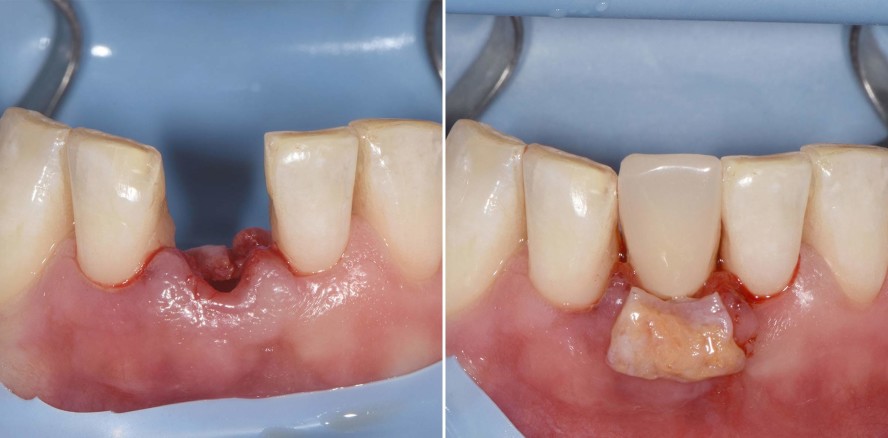

Der 45-jährige männliche Patient konsultierte die Zürcher Praxis des Autors nach Überweisung eines Privatzahnarztes. Er klagte über eine Stiftkrone in Regio 41, die sich gelöst hatte. Nach einem Unfall in seiner Jugend hatte er eine traumatische Fraktur seines linken unteren Schneidezahns erlitten. Infolgedessen war eine Wurzelbehandlung durchgeführt und der Zahn mit einem Stift und Goldaufbau sowie mit einer VMK-Krone versorgt worden (Abb. 1a und b). Die Krone war 22 Jahre lang beschwerdefrei in situ gewesen. Nach Entfernung des gelockerten Stiftaufbaus wurde eine Längsfraktur im Wurzelbereich erkennbar (Abb. 1c). Der verbleibende Zahn war somit nicht erhaltungswürdig.